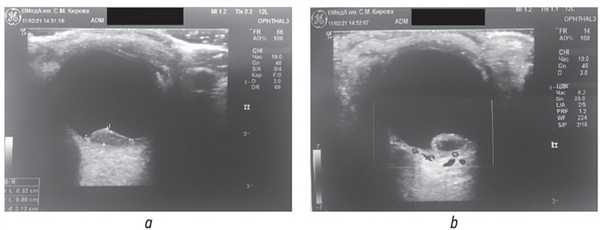

По данным ультразвукового исследования с доплеровским картированием в нижнем отделе глазного яблока было выявлено округлое образование неоднородной эхоплотности, размерами 0,32 × 0,80 см, с отсутствием сосудистого сигнала в центре образования (рис. 2).

Рис. 2. Ультразвуковое исследование: а — режим В-сканирования; b — режим доплеровского картирования